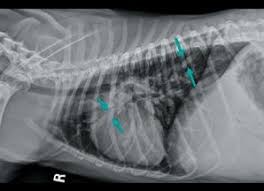

Lateral thoracic radiograph from a dog with a ventral alveolar pattern.

Lateral thoracic radiograph from a dog with a ventral alveolar pattern. That still leaves the question of why you should have recurrent pneumonia, unanswered and that is a question that will require further investigation. You can see on the left of the image a dark (relatively clear) lung. Pneumonia in people with lung cancer. The cause can be bacteria, a virus, or fungi. The problem here is that many things can enlarge the spleen above and beyond cancer. Note the increased soft tissue opacity in the lungs that partially obscures blood vessel margins. Various viruses, bacteria, and fungi can cause pneumonia. Differential diagnosis for common lung patterns in dogs and cats. I am a severe asthmatic and have had pneumonia on several occasions. This can happen when there is a high suspicion of cancer, for example, an enlarged spleen in a dog who is not acting right. Your veterinarian may recommend an fna and cytology or a biopsy, to confirm the diagnosis, and determine exactly what kind of lung cancer is present. Primary lung cancer are frequently located in the caudal (towards the hind end of the pet) lung lobes, however can be located in any lung lobe and are usually a single mass in the lungs, unless the tumor has spread.

Bacterial culture and drug sensitivity testing help the veterinarian to determine the best course of antibiotic treatment, if needed. His appetite is basically normal though his blood work shows that he is anemic. They did a cat scan and said the nod was.08 or 08 centimeters in dia. Note the increased soft tissue opacity in the lungs that partially obscures blood vessel margins. Bacterial pneumonia is an inflammation of the lung usually caused by bacterial or viral infection but can be caused by inhalation of an irritant. I am a severe asthmatic and have had pneumonia on several occasions. Your veterinarian may recommend an fna and cytology or a biopsy, to confirm the diagnosis, and determine exactly what kind of lung cancer is present. That still leaves the question of why you should have recurrent pneumonia, unanswered and that is a question that will require further investigation. The end stage of lung cancer in dogs is a very difficult time for dog owners as it's very hard to watch a beloved companion start giving up on life. Note the lobar sign with the caudal lung lobe. As these can also be caused by other disease, diagnostics include a full physical exam, blood work, radiographs, and may also require bronchoscopy with. A definitive diagnosis of lung cancer requires a sample of tissue (biopsy). This can happen when there is a high suspicion of cancer, for example, an enlarged spleen in a dog who is not acting right.